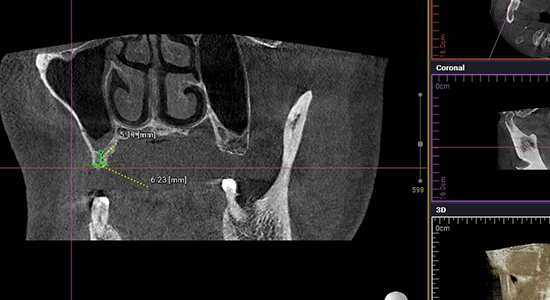

임플란트 시술을 위한 정밀진단

치아를 빼고 오래 방치하거나 치아를 잡고 있는 치조골이 많이 녹은상태에서 치아를 빼면 위쪽 턱뼈가 부족할 수 있습니다.

뼈이식 / 임플란트 식립공간 확보

잇몸을 절개하고 난 후 뼈를 넣고 상악동을 들어 올릴만한 작은 통로를 만들어 뼈이식할 공간과 임플란트 식립할 공간을 확보합니다.